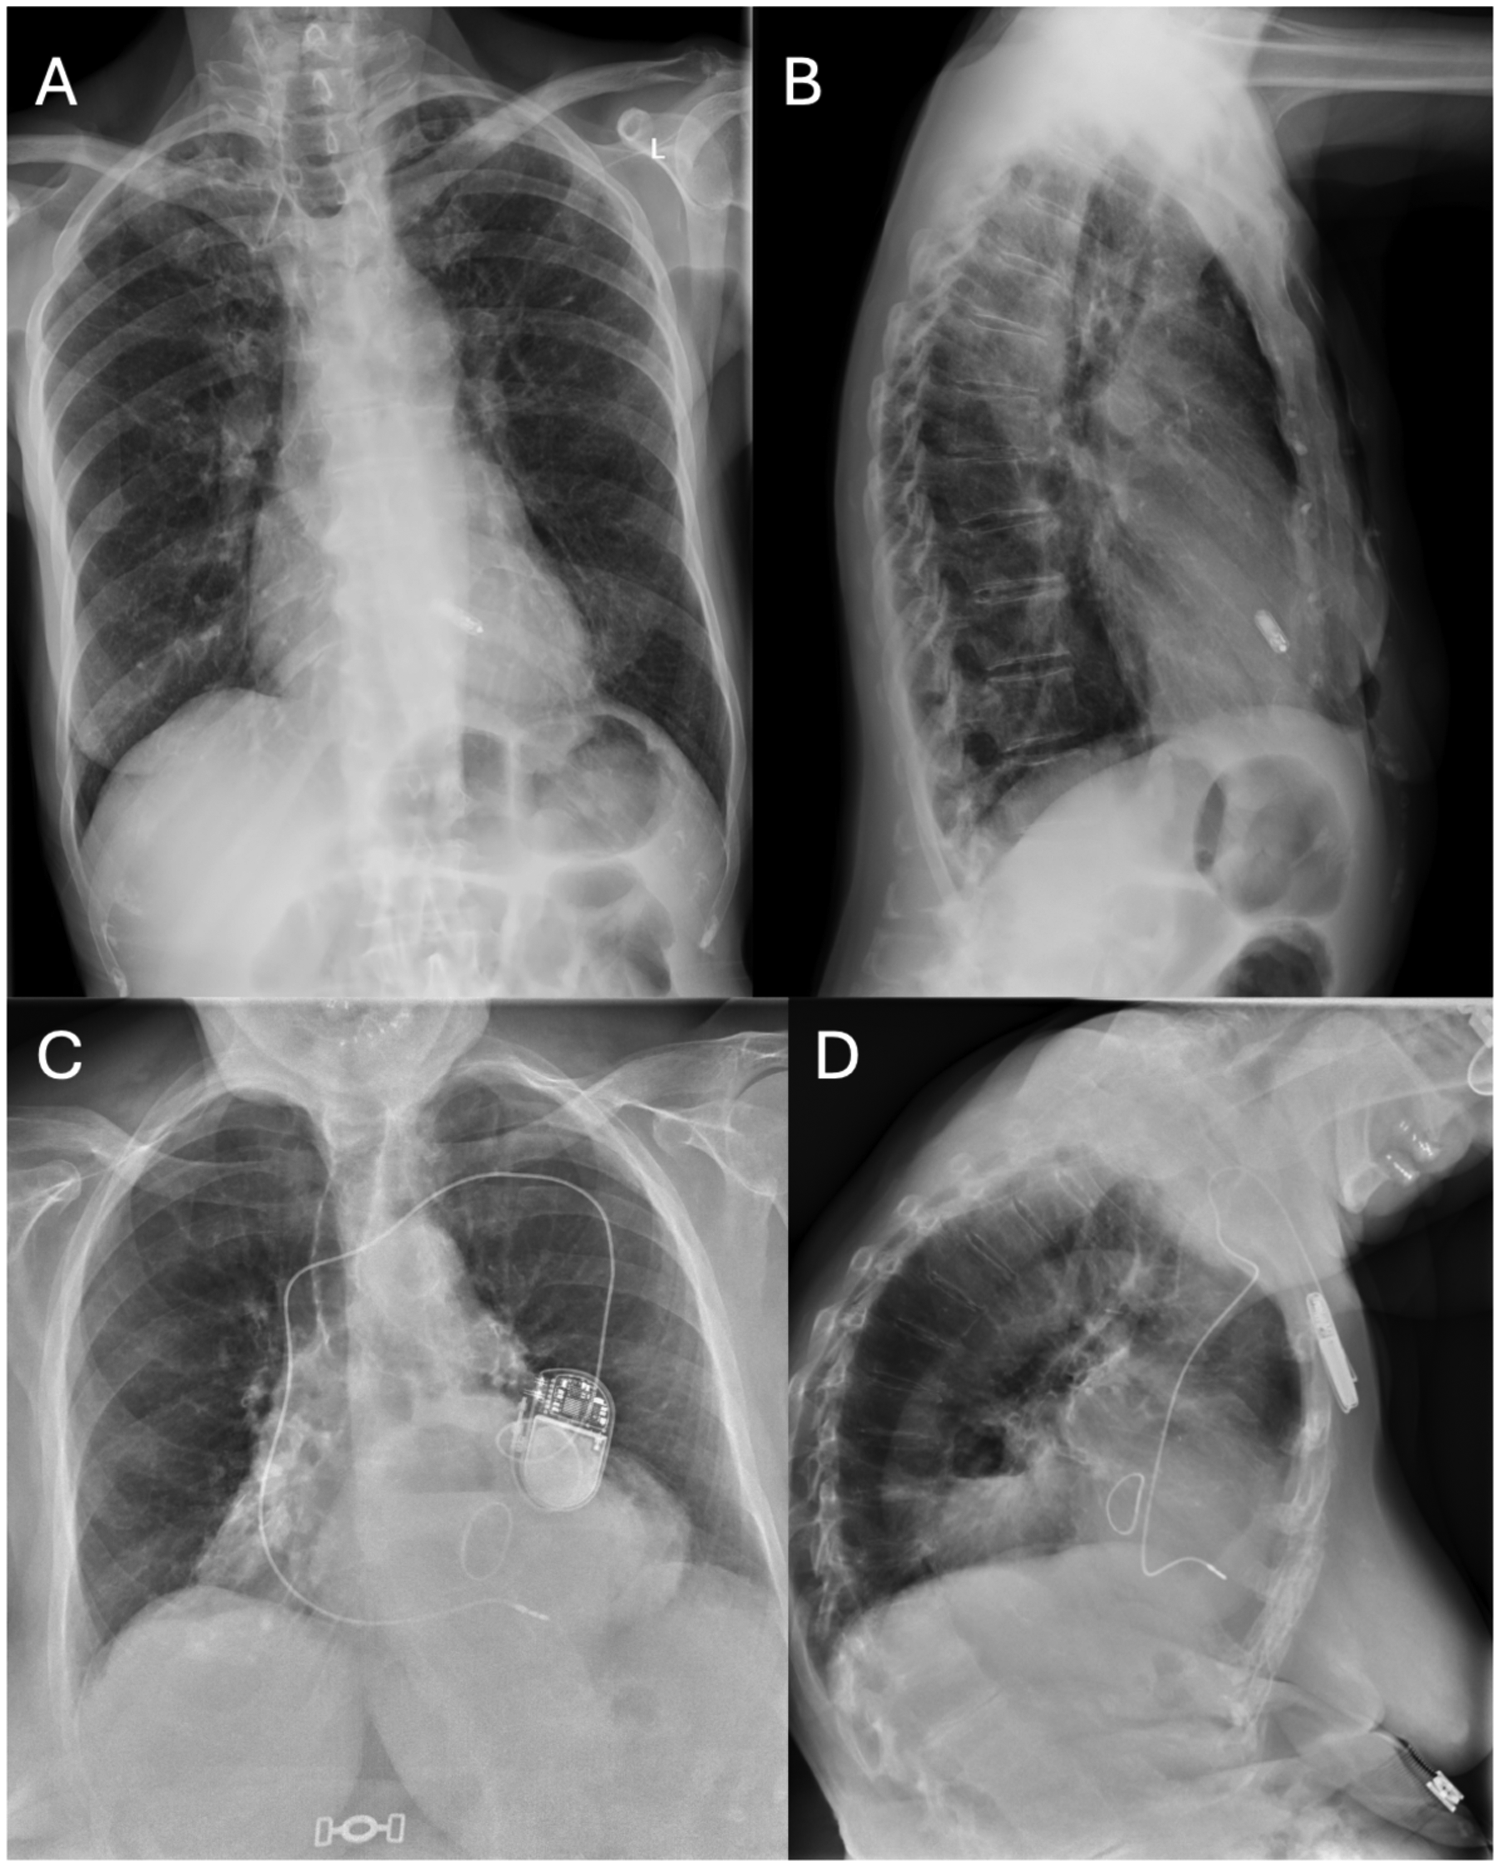

In the leadless group, the Micra™ VR system was implanted via femoral access following manufacturer instructions. In the standard pacemaker group, a transvenous single-chamber device was implanted via subclavian or axillary access. In both groups, a remote home monitoring system was activated to collect device data and facilitate early detection of complications, Figure 1.

Figure 1

Chest x-Ray of patients with leadless pacemaker vs conventional single-chamber transvenous pacemaker. Chest x-Ray of patients with leadless pacemaker vs conventional single-chamber transvenous pacemaker. (A) Chest x-Ray of a patient with leadless pacemaker (postero-anterior view); (B) Chest x-Ray of a patient with leadless pacemaker (latero-lateral view); (C) Chest x-Ray of a patient with a conventional single-chamber transvenous pacemaker (postero-anterior view); (D) Chest x-Ray of a patient with a conventional single-chamber transvenous pacemaker (latero-lateral view).